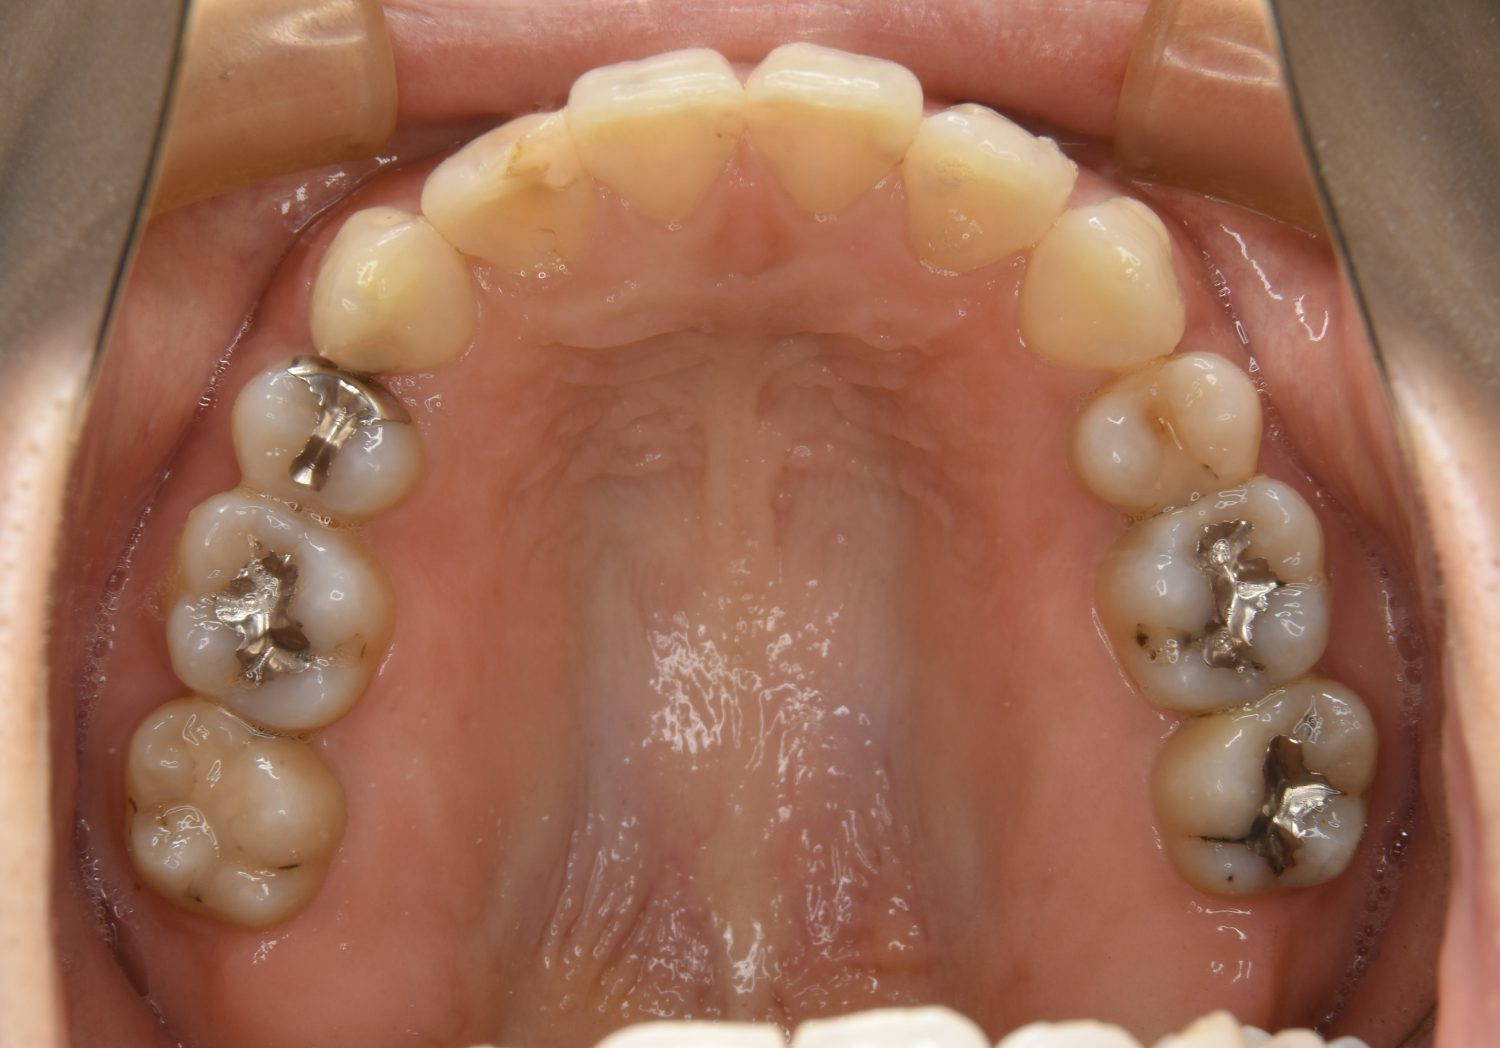

前歯部開咬の症例紹介①

Before

主訴

前歯が開いているのが気になる。

治療内容

上リンガルブラケット(舌側装置)、下ラビアルブラケット(唇側装置)に矯正用アンカースクリューを併用し非抜歯で治療を行いました。

治療費

1,200,000 円(税込)

治療期間

33ヶ月

通院回数

34回

想定されたリスク

※歯根吸収、歯肉退縮、歯髄壊死、顎関節症状

上下の前歯が開いており前歯では全く噛めていない状態でした。臼歯の圧下を行うことで前歯でも咬合できるようになり機能面のみでなく審美面も著しく改善しました。